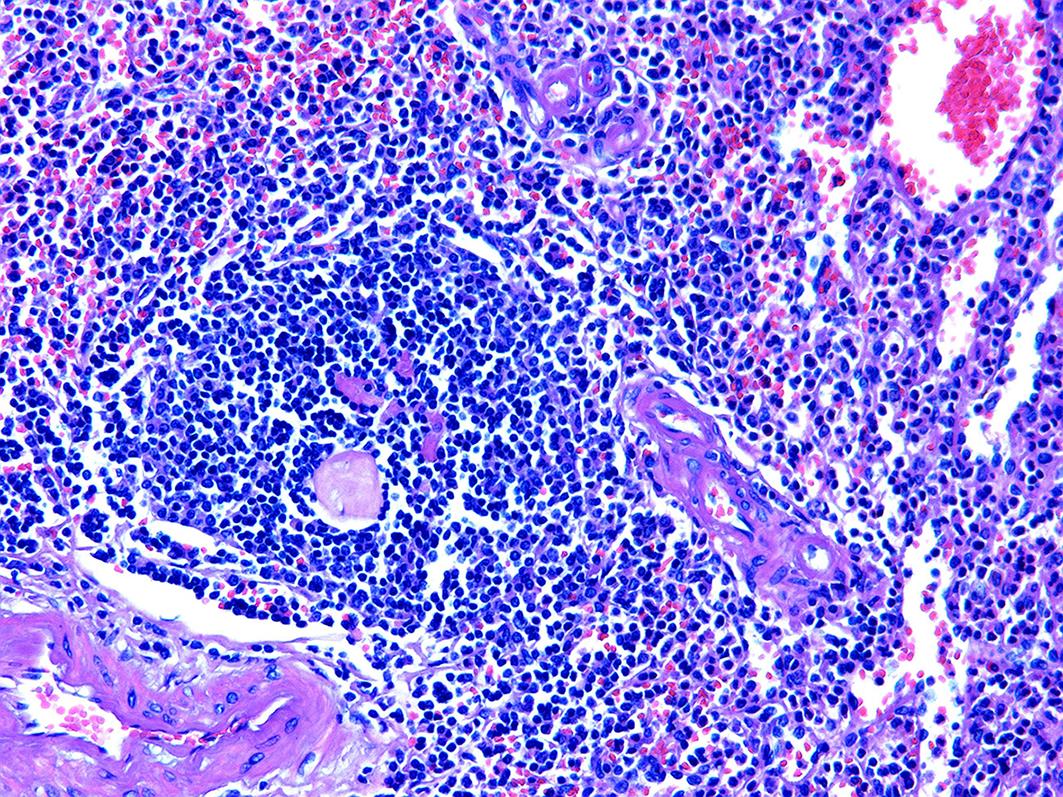

胰腺内副脾误诊2例报告

摘要(1364) HTML (331) PDF (1188KB)(157)

摘要:

副脾是指正常脾脏以外存在的,与主脾结构相似,有一定功能的脾脏组织,其中完全被胰腺包裹的胰腺内副脾(IPAS)发生率仅为2%,因其临床症状不典型,影像学特征与胰腺神经内分泌肿瘤、胰腺实性假乳头状瘤以及其他胰腺占位性病变较为相似,临床上容易误诊。本文报道了2例分别被误诊为胰腺神经内分泌肿瘤和胰腺实性假乳头状瘤的IPAS患者,并分析误诊原因,总结诊疗经验,以期提升临床对IPAS明确鉴别诊断的认识。